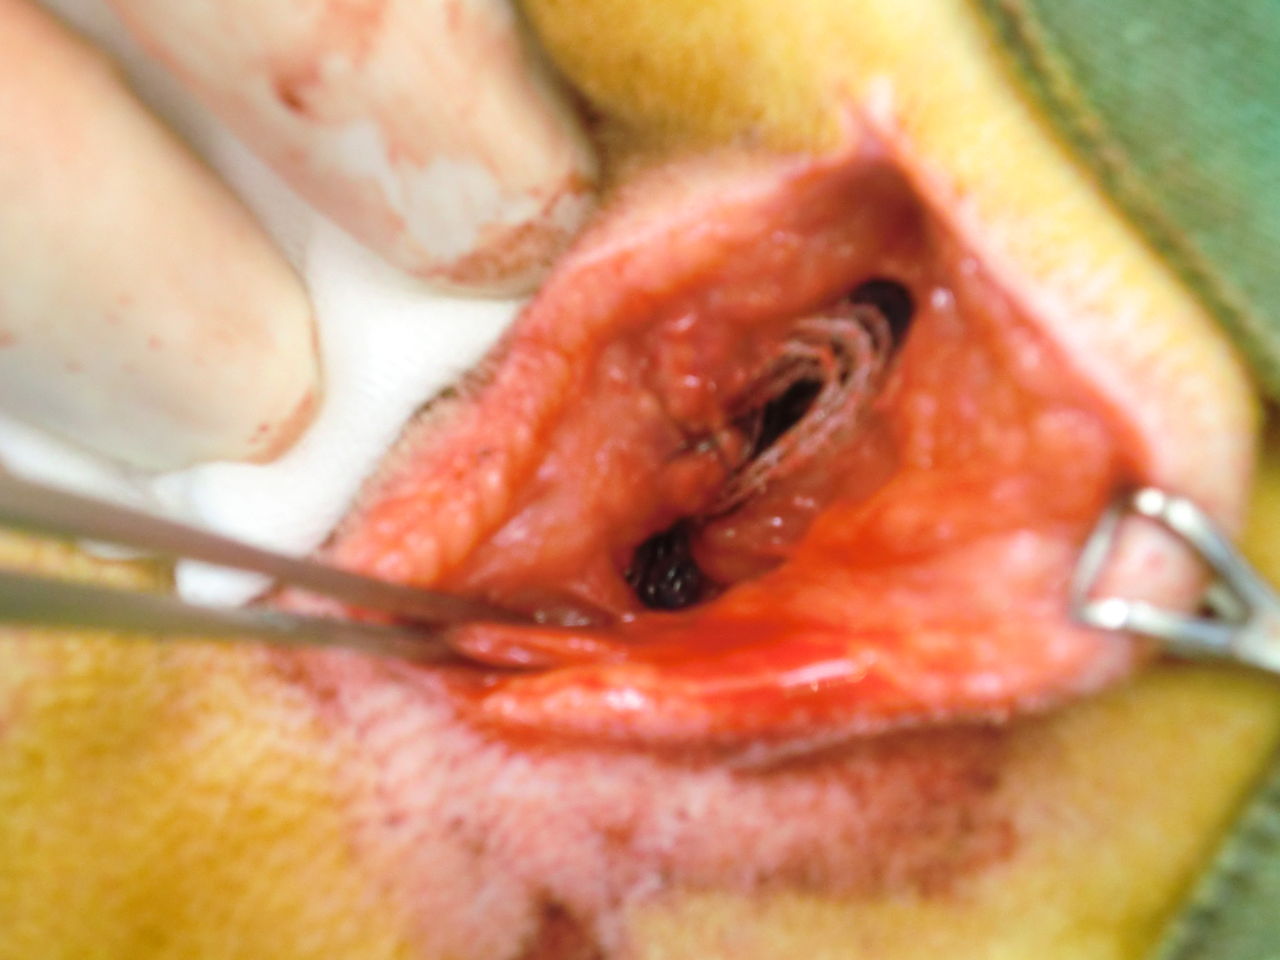

会陰ヘルニア整復術 full ver 専門医に学ぶ外 etv store